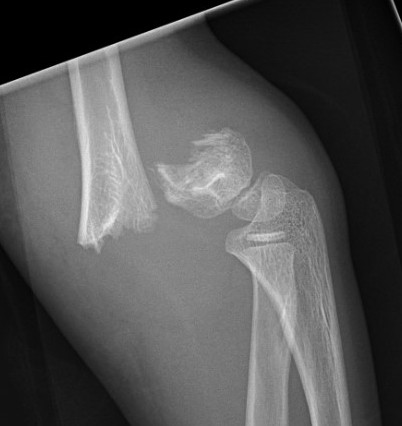

Gartland Classification Extension Fractures

Gartland I - Undisplaced

- < 2 mm

- anterior and posterior cortices intact

Gartland II - Displaced with intact posterior cortex

- > 2 mm

- anterior humeral line passess anterior to capitellum

- posterior periosteum is intact

Gartland III - Displaced, nil cortical contact

- completely displaced

- posteromedial or posterolateral

Gartland IV - Nil cortical contact with complete periosteal disruption

Extremely unstable at surgery in both flexion and extension planes

Modified by Wilkins

Type IIB Rotated

Type IIIA Posteromedial

Commonest

- distal fragment goes posteromedial

- cause cubitus varus

- injures radial nerve which is tethered over lateral spike on proximal fragment

- manage by pronation which tightens medial periosteal hinge

Type IIIB Posterolateral

Distal fragment goes posterolateral

- causes cubitus valgus

- tend to ER

- injuries median nerve & brachial artery

- these get tethered over medial spike on proximal fragment

- manage by supination which tightens lateral periosteal hinge

The position of stability is achieved with the thumb pointed towards the side of the periosteal disruption